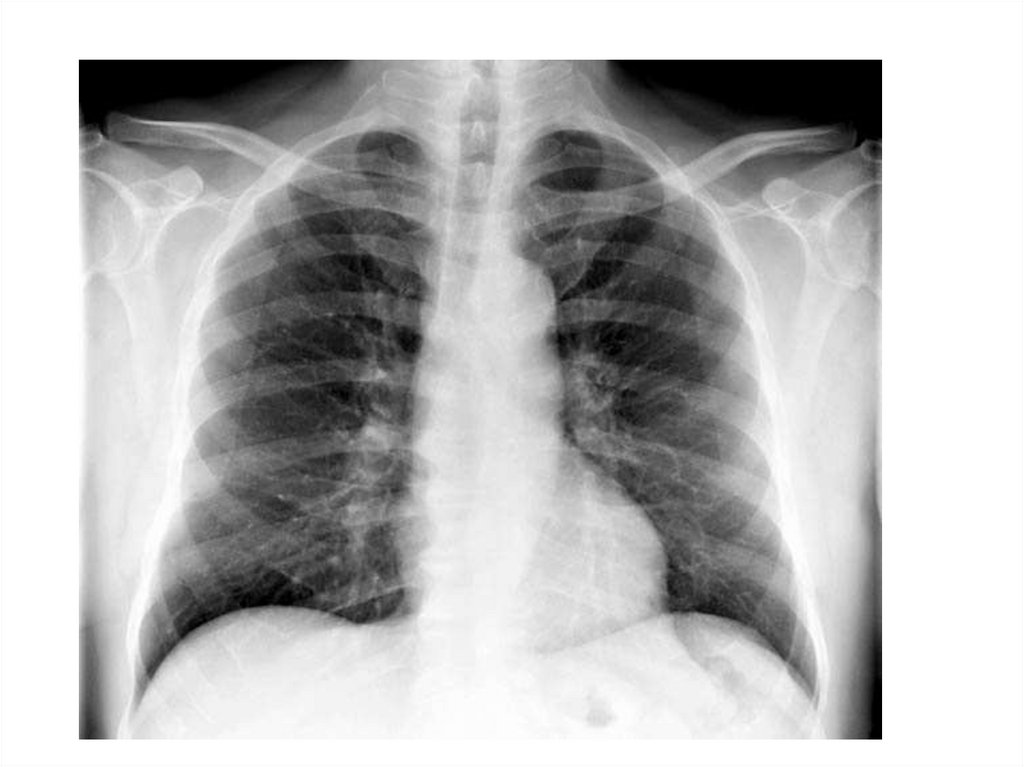

Лучевое исследование лёгких, сердца и крупных сосудов

Лучевое исследование лёгких,

сердца и крупных сосудов

Рентгенография